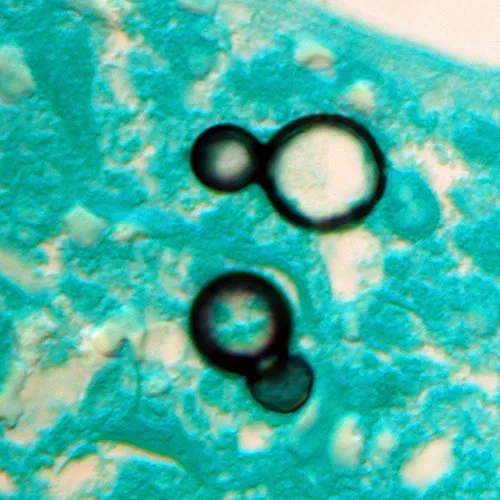

- Yeast form: Large, round, with a single Broad-Based Bud. 📌 "Blasto buds broadly."

⭐ Pathogenesis Hallmark: The yeast form evades phagocytosis partly due to its thick wall and characteristic single, broad-based bud.

- Microscopy: Direct visualization of large, round yeast with a single, broad-based bud.

- Look for large yeast cells with single, broad-based buds on microscopy.